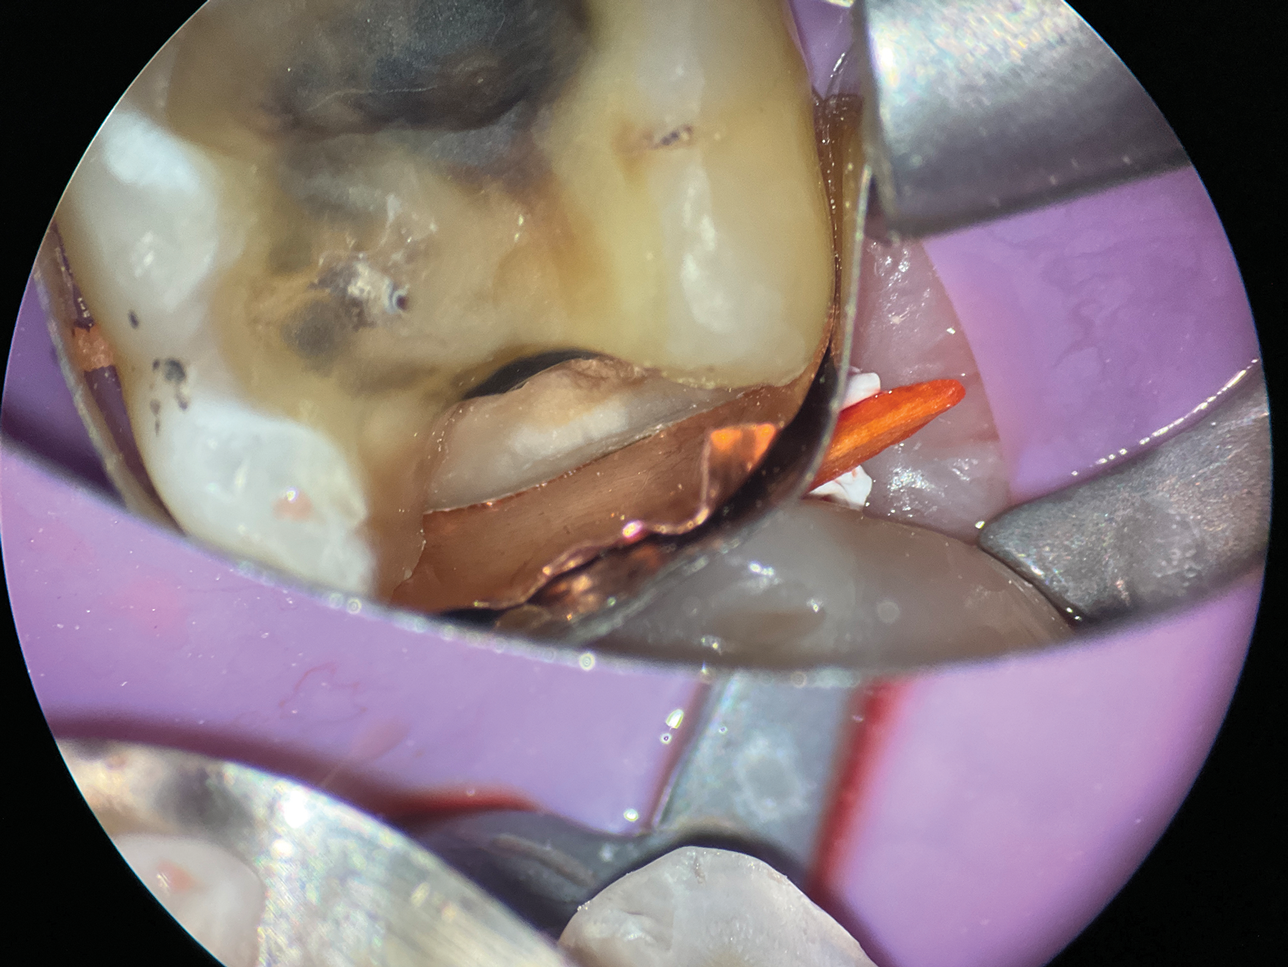

(10.) A close-up distolingual view of a mandibular molar after the removal of caries that extended to the bone level.

Figure 10